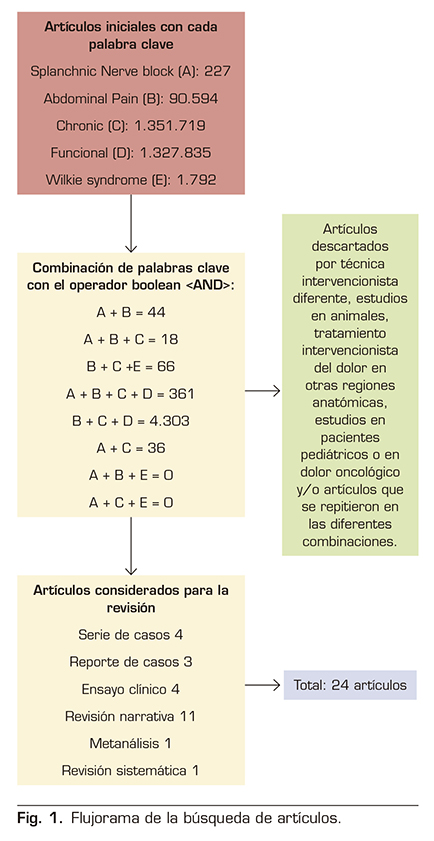

Se realizó una revisión narrativa no sistemática basada en una búsqueda de literatura en la base de datos PUBMED, que incluyó artículos de metanálisis, revisiones sistemáticas, ensayos clínicos, revisiones narrativas y series de casos. Los términos de búsqueda (MeSH) fueron: “Splanchnic Nerve block”, “Abdominal Pain”, “Chronic”, “Functional” y “Wilkie síndrome”.

Se obtuvieron un total de 2.772.167 artículos. La combinación de las 5 palabras clave no arrojó ningún resultado. Se realizó una combinación entre ellas y se obtuvieron los artículos que se tomaron en cuenta. El resto se descartaron por ser estudios en animales, técnica intervencionista diferente, tratamiento intervencionista del dolor en otras regiones anatómicas, estudios en pacientes pediátricos o en dolor oncológico y/o artículos que se repitieron en las diferentes combinaciones (Figura 1).